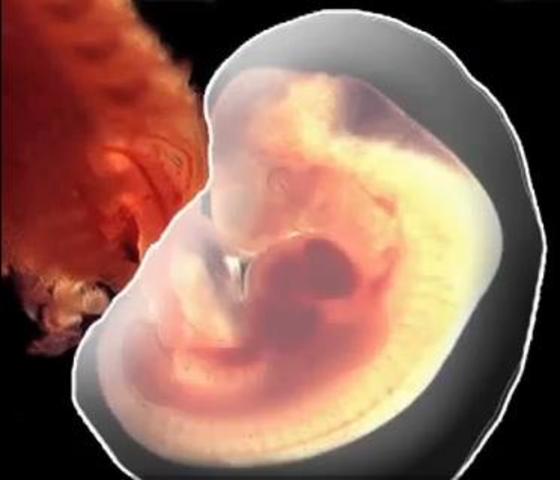

• 8 semanas. Características externas

8 semanas. Características externas

-La cabeza es casi la mitad de la longitud del feto

-La flexión cervical en de cerca de 30 grados

-Están presentes genitales externos indiferenciados

-Los ojos son convergentes

-Los párpados están fusionados

-Desaparece la cola

-Las narinas están ocluidas por unos tapones epiteliales

• 8 semanas. Características internas

8 semanas. Características internas

-Se produce la herniación del intestino medio hacia el cordón umbilcal

-La porción extraembrionaria de la alantoides ha degenerado

-Se forman los conductos y los alveólos de las glandulas lacrimales

-Los conductos paramesonéfricos comienzan a regresar en los varones

-Se produce la recanalización de la luz del tubo intestinal

-Los pulmones comienzan a tomar apariencia glandular

-El diafragma está completo

-Comienza la primera osificación en el esqueleto

-Sistema definitivo del arco aórtico